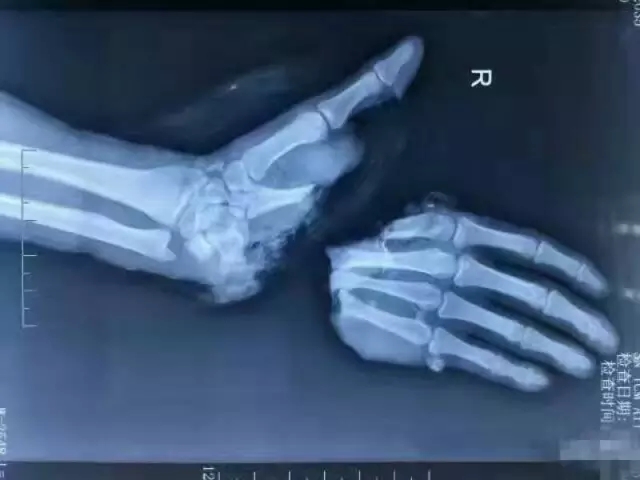

剁了手,要怎么接回去?

答案就是——“断肢再植”!

1963年严冬,上海青年工人王存柏因操作不慎,被冲床纵向切断右手。受伤的工人及其断手被紧急送到上海第六人民医院。

连续8个小时的手术,陈中伟等人完成了世界首例断手再植。在此后的几个月里,陈中伟和同事全力以赴,闯过道道难关,才使得这只失而复得的手转危为安,有了正常体温、有了知觉、可以伸屈活动、能提重物、能写字,经过方方面面测试,证明断手已成功接治。

手指、足趾血管细,肉眼看不清,必须借助光学工具,医生才能在最细仅1毫米的血管上“穿针引线”。显微外科技术的应用,使断指再植成活率由50%左右提高到90%以上,各种皮瓣移植,拇手指再造、周围神经修复、吻合血管的骨移植等新成果不断问世,显微外科在我国得到了飞速发展,较早并一直跻身于国际领先地位。